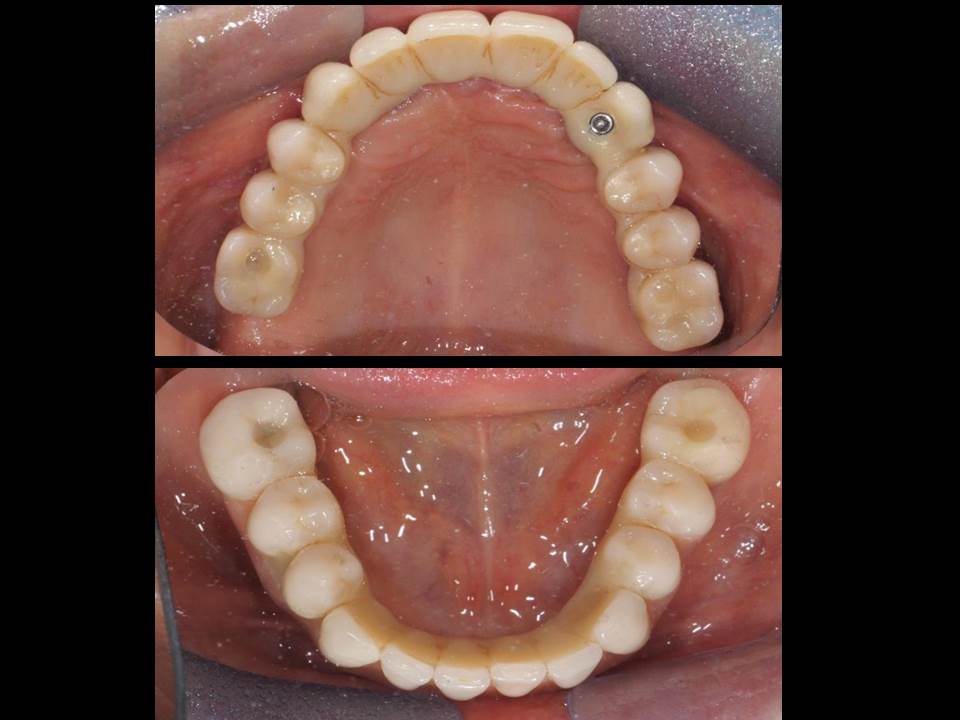

CASOS CLÍNICOS